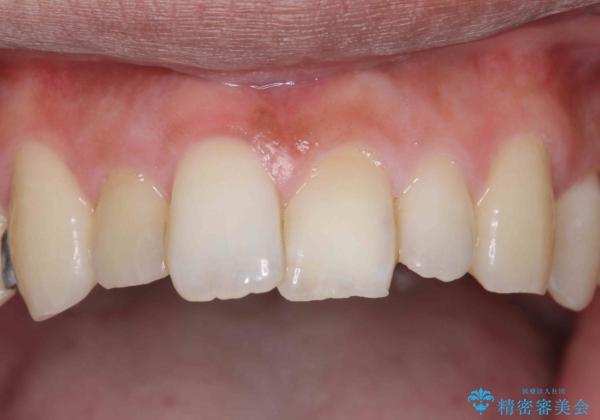

前歯をやむなく抜歯 ブリッジに 治療ついでに歯並びもよく

以上を説明したところ、早めに抜歯を行いブリッジにしていくことを希望されたため治療開始しました。

- 78.1万円 内訳(前歯ブリッジ 右上③2➀:ジルコニアクラウンスペシャル15.4万円×3、仮歯1.1万円×3 左上1:精密根管治療再治療 9.9万円×1、ファイバーコア2.2万円、ジルコニアクラウンスペシャル15.4万円、仮歯1.1万円)費用は治療当時の料金となります